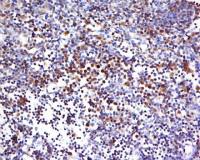

| 产品图片 |  Sample: MDA-MB-231(Human) Cell Lysate at 40 ug Primary: Anti-PALB2 (bs-0588R) at 1/300 dilution Secondary: IRDye800CW Goat Anti-Rabbit IgG at 1/20000 dilution Predicted band size: 131 kD Observed band size: 131 kD  Sample: HepG2(Human) Cell Lysate at 40 ug Primary: Anti-PALB2 (bs-0588R) at 1/300 dilution Secondary: IRDye800CW Goat Anti-Rabbit IgG at 1/20000 dilution Predicted band size: 131 kD Observed band size: 131 kD  Independently Validated Antibody, image provided by Science Direct, badge number 029682:Formalin-fixed and paraffin embedded pig skeletal muscle labeled with Rabbit Anti-PALB2 Polyclonal Antibody, Unconjugated (bs-0588R) at 1:100 for one hour at room temperature followed by conjugation to the secondary antibody Mach2 rabbit HRP-Polymer for 30 min at room temperature and DAB staining.  Independently Validated Antibody, image provided by Science Direct, badge number 029682:Formalin-fixed and paraffin embedded human breast cancer labeled with Rabbit Anti-PALB2 Polyclonal Antibody, Unconjugated (bs-0588R) at 1:100 from one hour at room temperature followed by conjugation to the secondary antibody Mach2 rabbit HRP-Polymer for 30 minutes at room temperature. Positive Control, the staining is correct.  Tissue/cell: human breast carcinoma; 4% Paraformaldehyde-fixed and paraffin-embedded; Antigen retrieval: citrate buffer ( 0.01M, pH 6.0 ), Boiling bathing for 15min; Block endogenous peroxidase by 3% Hydrogen peroxide for 30min; Blocking buffer (normal goat serum,C-0005) at 37℃ for 20 min; Incubation: Anti-PALB2 Polyclonal Antibody, Unconjugated(bs-0588R) 1:200, overnight at 4°C, followed by conjugation to the secondary antibody(SP-0023) and DAB(C-0010) staining  Blank control: Hela(blue), the cells were fixed with 2% paraformaldehyde (10 min) and then permeabilized with ice-cold 90% methanol for 30 min on ice.. Isotype Control Antibody: Rabbit IgG(orange) ; Secondary Antibody: Goat anti-rabbit IgG-FITC(white blue), Dilution: 1:100 in 1 X PBS containing 0.5% BSA ; Primary Antibody Dilution: 1μg in 100 μL1X PBS containing 0.5% BSA(green). |